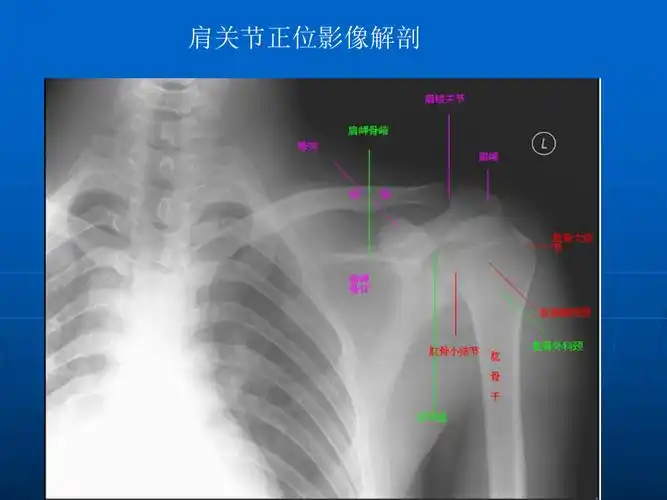

肩关节的摄影体位课件ppt